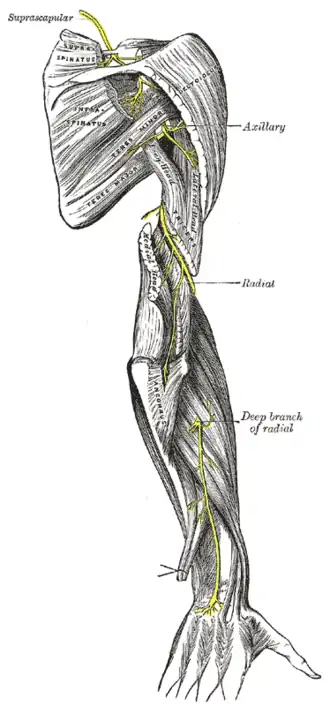

| Radial nerve compression is an example of nerve compression syndrome | |

Causes

Certain occupations, postures, and activities can put prolonged pressure on a nerve. The term "Saturday night palsy" is used for a radial nerve injury caused by prolonged compression of the nerve at the spiral groove. The origin of the term is due to the association of the condition with a night spent in alcoholic stupor with the arm draped over a chair or bench. Mechanical compression of the radial nerve in the spiral groove can also occur as a result of the continuous use of crutches or prolonged kneeling in a "shooting" position.[14] The so-called "cyclist palsy" is caused by prolonged grip pressures on handlebars, and has been postulated to be an entrapment neuropathy of the ulnar nerve in the Guyon canal of the wrist.[15] Occupational exposure to forceful handgrip work and vibration, such as construction workers, increased the risk for surgical treatment of radial nerve entrapment.[16] Posture induced common peroneal nerve (CPN) palsy is usually produced during the prolonged squatting or habitual leg crossing while seated, especially in Asian culture and is manifested by the onset of foot drop.[17] One sport-related cause of lateral femoral cutaneous nerve entrapment is seen in scuba divers where the weight belt worn around the waist directly compresses the nerve.[18] Prolonged periods of cycling can be associated with pudendal nerve entrapment, as there is often direct compression on the pudendal nerve between the nose of the bicycle seat and pubic bone.[19] Tight fitting goggles can put pressure on the supraorbital nerve, also known as "swimmer's headache".[20] Tight fitting handcuffs can compress the superficial branch of the radial nerve, known by several names such as Cheiralgia paresthetica, Wartenberg's syndrome, and handcuff neuropathy.[21] The use of a thick wallet in the rear pocket can compress the sciatic nerve when sitting.[22]

| Radial | axilla | Radial nerve compression |

| Radial | spiral groove | Radial nerve compression |

| Radial (Posterior interosseous) | proximal forearm | posterior interosseous nerve entrapment |

| Radial (Superficial radial) | distal forearm | Wartenberg's Syndrome |